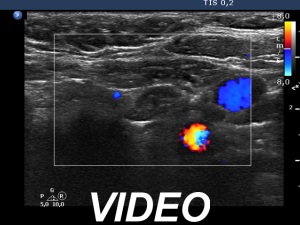

Ultrasonography. The thyroid was echonormal. According to the PET-positive lesion, there was a moderately hypoechoic nodule in the middle-dorsal part of the left lobe. The lesion presented with perinodular blood flow. In the transverse section, it appeared that there was another nodule in the lower pole of the lobe. At the same time, based on the longitudinal section, it was not an oval, nodule-like lesion. The mass proved to be longitudinally elongated in the caudal direction and was avascular.

An anatomical structure running perpendicular to the transducer looks round or oval, and it can look deceptively like a discrete lesion. If this occurs in the thyroid region, it can be mistaken for a nodule. The most common examples of this are the carotid artery, the jugular vein, and the esophagus, the latter usually appears on the dorsal surface of the left lobe of the thyroid gland. The key is always to examine the patient in two perpendicular planes. An examination parallel to the anatomical structure (in this case in the longitudinal section) shows that it is a tube-like, longitudinal structure. In this case, it was very likely a dorsal muscle.

A muscle used to be avascular on Doppler mode.